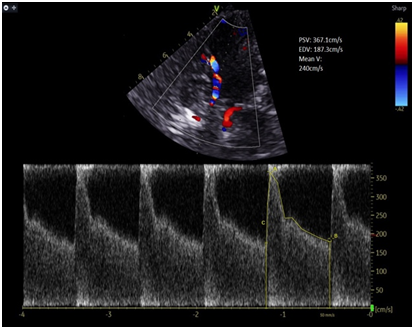

Case Description: A 53-year-old gentleman presented with a modified Fisher grade IV subarachnoid haemorrhage secondary to a ruptured anterior communicating artery (ACOM) aneurysm, treated with endovascular coiling. On post-bleed day 4, he developed symptomatic vasospasm. Despite maximal therapy including oral and intra-arterial nimodipine and hypertensive therapy in the intensive care unit, his neurological condition deteriorated. An ultrasound-guided left stellate ganglion block at C6/7 level was performed using 8 mL of 0.5% levobupivacaine with clonidine 75 mcg. The patient demonstrated immediate neurological improvement, with a reduction in left middle cerebral artery transcranial Doppler (TCD) mean velocity from 246 cm/s to 110 cm/s, without any procedural complications.